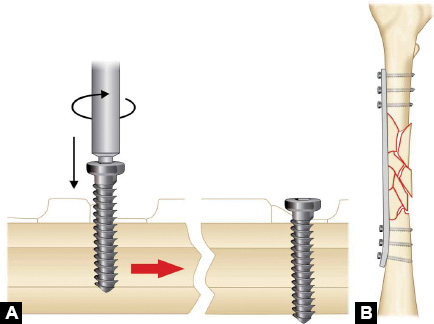

Dynamic compression plate (Fig. 1.41A): In dynamic compression plating tightening of eccentrically placed screws across plate cause axial compression of fracture.

In dynamic compression plate slots for compression have a sloping surface at one end. Centrally placed screw compress the plate against bone. Now in opposite fragment screws are placed eccentrically and when tightened plate moves and compresses the fracture (Newton's third law of motion).

-

The tension band principle: Tensile/distractive forces are converted into compressive forces by applying device (either plate or tension band wire) on convex surface or tension surface of a fractured bone (Fig. 1.43). Here the patellar fragments are being distracted by quadriceps above and ligament patellae below. A wire has been tied on the convex side of patella. This will get stretched due to patellar distraction by quadriceps and just like a stretched rubber band it will reciprocally exert compression pull upon this stretch to compress the fracture (Newton's third law of motion).

Fractures where tension band principle is commonly used are listed in Box 1.11.